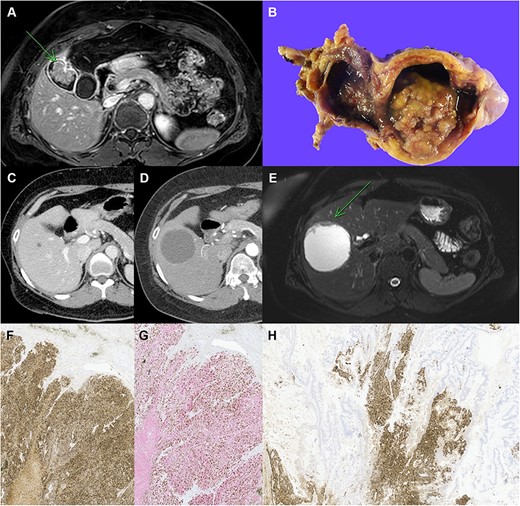

Clinicopathological images of the patient. (A) Preoperative MRI showing GB cancer, (B) gross specimen of GB with papillary tumor, (C, D) follow-up imaging showing the increased size of cystic lesion in the liver, (E) MRI showing cystic mass in segment V with enhancing mural nodule and wall thickening, (F) immunohistochemical staining with chromogranin A, (G) synaptophysin (red) and Ki-67 (brown) double staining in neuroendocrine carcinoma of the liver, (H) chromogranin A staining in the GB tumor, which reveals neuroendocrine component (original magnification: ×100).

For further information, magnetic resonance imaging (MRI) and positron emission tomography (PET)-CT scan were performed, and MRI also revealed a 3.5 cm sized enhancing villous mass in GB body, suggesting GB cancer (Fig. 1A). Two tiny low attenuating lesions in segment V and VI of the liver were likely to be cysts, suggesting non-malignancy. PET-CT revealed increased fludeoxyglucose (FDG) uptake in the GB body mass, which was suspected to be malignant, and discernible FDG uptake was not found in the liver.

Based on her imaging findings, laparoscopic radical cholecystectomy was planned under the impression of GB cancer. The specimen showed a 4-cm-sized papillary mass and pathologic examination confirmed well-differentiated adenocarcinoma without lymph node metastasis (T2aN0M0, Stage IIA) (Fig. 1B).

After the surgery, the patient received adjuvant gemcitabine chemotherapy and was followed-up in outpatient settings. A series of follow-up CT showed a growing cyst in the S5 liver segment (Fig. 1C and D). Therefore, MRI was performed for differential diagnosis, which showed a growing 7-cm-sized cystic mass with enhanced mural nodule and wall thickening (Fig. 1E). Right lobectomy of the liver was planned for the possibility of malignancy.

After the surgery, pathological findings of the specimen revealed neuroendocrine carcinoma (NEC) sized 8 cm. The tumor contained extensive necrosis, with mitotic index 2/10 HPF and focal glandular differentiation of < 5% (Fig. 1F). The Ki-67 index was about 70%, and the subtype of the NEC was large cell NEC (LCNEC) (Fig. 1G).

The most likely diagnosis was metastatic tumor of the liver, and thus thorough diagnostic work-up for primary tumor site was performed. Ga-68 DOTATOC PET-CT was performed; however, the site of primary origin could not be located. In extension of finding the origin of the NET, a review of the previously resected GB specimen was conducted. The review found a neuroendocrine component in the specimen, which was previously unseen. The neuroendocrine component was positive for chromogranin A, synaptophysin and CD56 in immunohistochemical staining, and the specimen was rediagnosed as MiNEN consisting of adenocarcinoma and LCNEC (Fig. 1H).